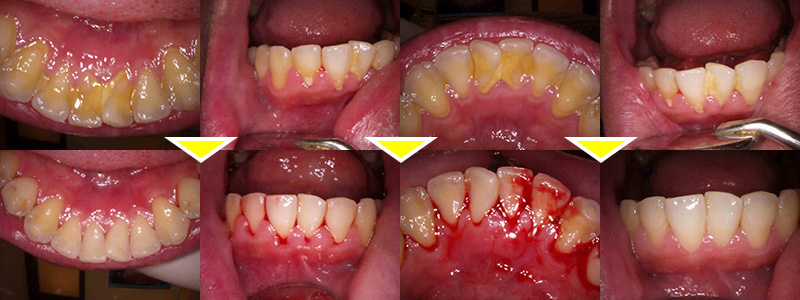

下顎前歯部に縁上歯石、全額的に縁下歯石の沈着の歯周病治療症例

下顎前歯部に縁上歯石が目立ち、全額的に縁下歯石の沈着も見受けられたため、歯周病治療を行うことを提案しました。

歯石が多かったこととプラークコントロール不良のため歯肉の腫脹、発赤が目立ったため、初日は縁上歯石の除去、プラークコントロールのしやすい環境にし、ブラッシング指導をメインに行いました。

1週間後 プラークコントロールの改善により表面的な歯肉の腫脹、発赤の改善がみられたため縁下歯石の除去(スケーリングルートプレーニング)を行いました。

2週間後 歯肉の内面の炎症も引き、より引き締まった歯肉に改善、出血量も軽減し、全額的なプラークコントロールも改善されました。